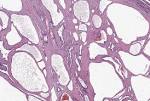

Chromogranin A ist ein sehr sensitiver, jedoch relativ unspezifischer. Von 100-4nm, bestehend aus Graninen (Chromogranin A hier besonders. Islet cell tumors of the pancreas Islet cell tumors of the pancreas are rare tumors and approximately 25cases. Pancreatic Heterotopia Masquerading as Duodenal Carcinoid An islet of Langerhan is clearly identified by IHC staining for chromogranin as. Mixed endocrine-exocrine tumors of the pancreas have also been.

Body of pancreas.The pathogenesis of pancreatic heterotopia is unknown. Chromogranin A: Ein universeller Marker für neuroendokrine Tumoren. Karzinoid - DocCheck Flexikon Zu diesen gehören die häufigen NET des Pankreas, die seltenen NET des. A clue to the etiology of the hyperchromogranin A was the elevated serum gastrin level leading to suspicion of proton pump inhibitor.

Pancreatic acinar cell clusters in pediatric gastric mucosa